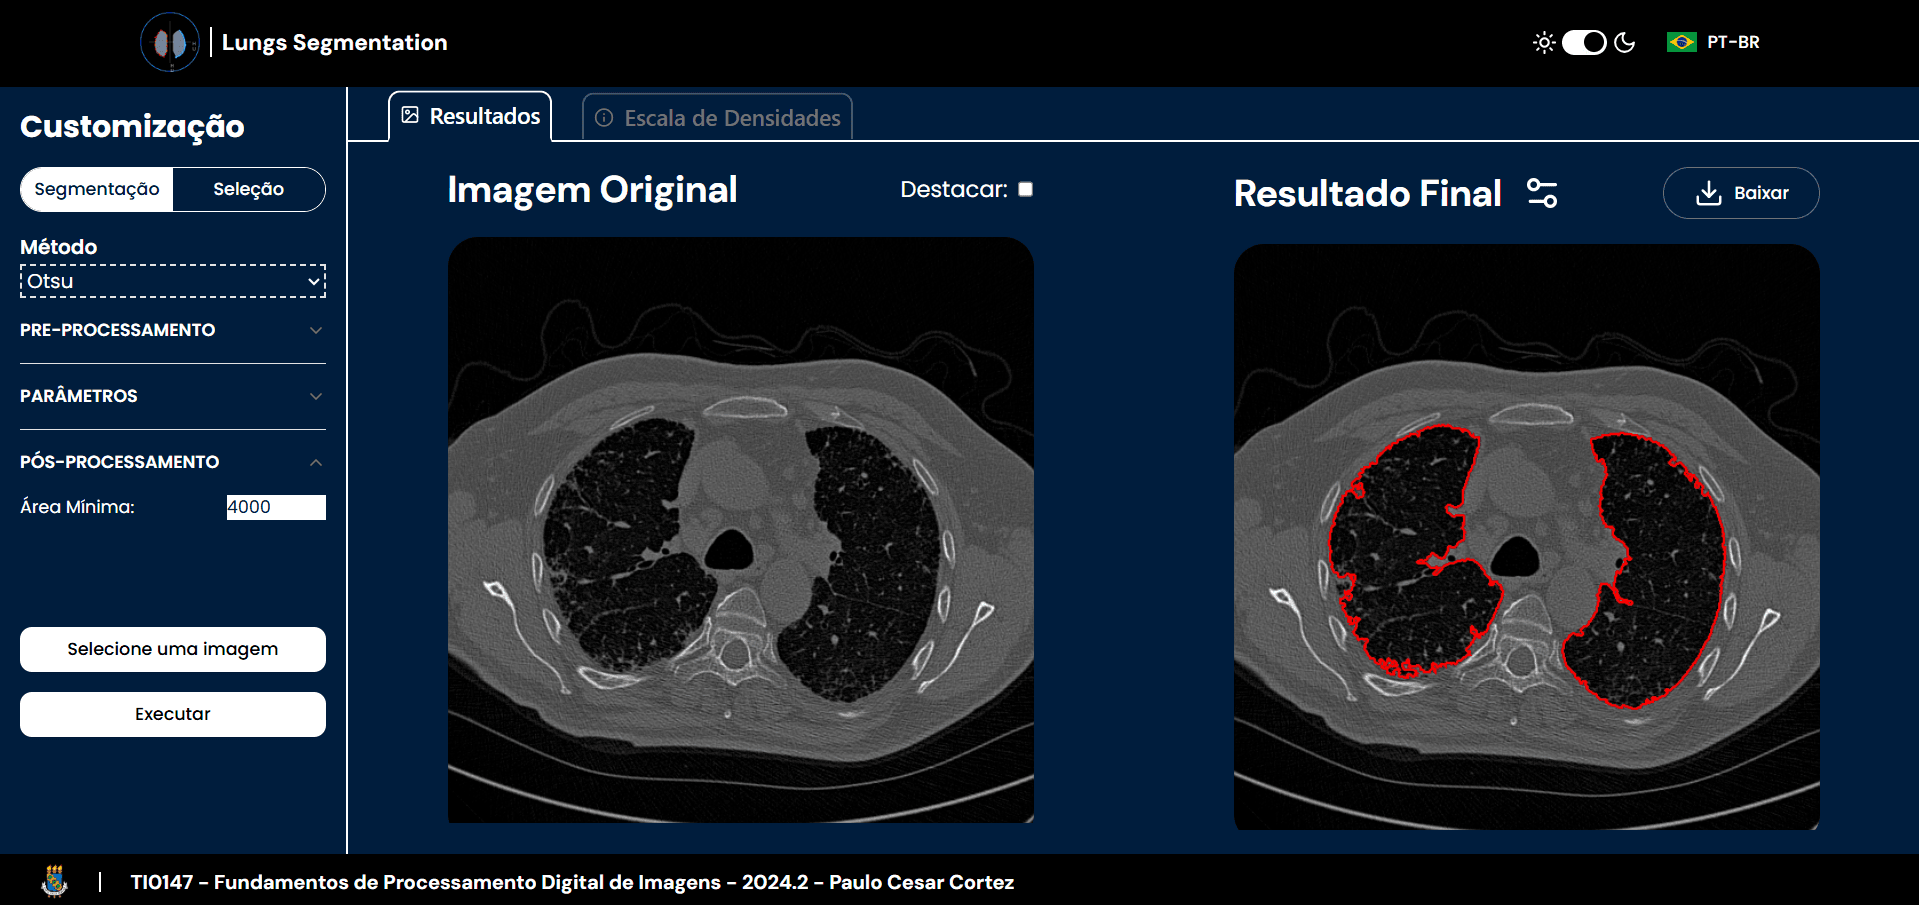

Lung Segmentation

A tool for automated lung segmentation from DICOM files, utilizing a Python-based backend for efficient processing.